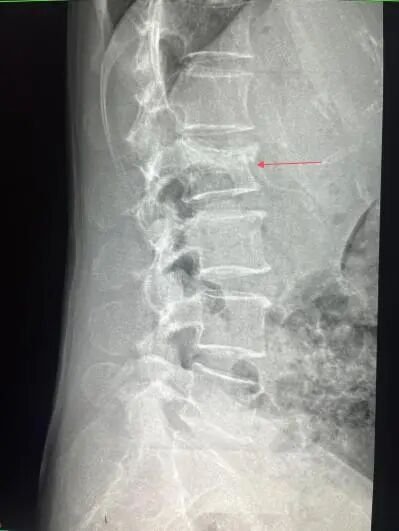

这类骨折因发病隐匿,被称为“沉默的骨折”。多数患者无明显摔倒或外伤史,可能只是弯腰抱孩子、打喷嚏、用力咳嗽等日常动作,就引发腰部剧痛。

核心原因是骨质疏松导致骨骼变脆,椎体无法承受身体重量或日常活动压力,进而发生微小或明显的压缩性骨折。其典型表现为翻身、起床、改变姿势时疼痛剧烈加重,安静平躺时缓解,部分患者还会逐渐出现驼背、身高变矮。

他呼吁,老年朋友若出现持续腰疼或相关伴随症状,应尽早到医院通过X光片、核磁共振MRI等检查明确病因,及时接受针对性治疗。“腰疼是身体发出的重要警报,及时干预才能避免小毛病拖成大问题,让老年人拥有无痛、自由活动的晚年生活。”